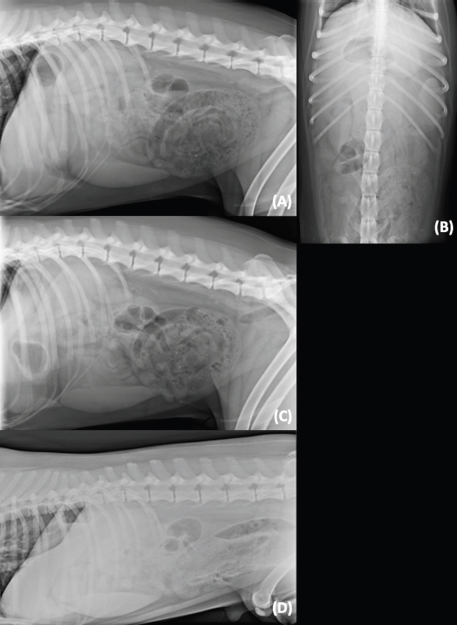

The presence of variable gas-capped fluid lines has been reported as a radiographic sign of mechanical gastrointestinal ileus in the HB view (Gibbs and Pearson, 1973; Harlow et al., 1993). This study confirms that 78.8% of the mechanical ileus cases exhibit this sign. However, this is not specific as 30.3% of the without mechanical ileus cases also have this similar radiographic sign (Fig. 2). Thus, the presence of gas-capped fluid lines in the HB view needs to be interpreted carefully and it is not a pathognomonic sign for mechanical ileus. However, it may suggest mechanical ileus and need further investigation.

Fig. 2. Left-to-right lateral HB views in sternal recumbency of two different patients. (A) A dog with mechanical ileus due to a gastro-jejunal linear foreign body. Note the presence of different levels of the gas-capped fluid lines in the small intestine. Additionally, there is a curvilinear radiopaque structure in the stomach, which was not identified in the standard VB views but recognized on the HB view. (B) A dog diagnosed with gastrointestinal intoxication secondary to mushroom ingestion in group P. Note the presence of the different level of gas-capped fluid lines in the small intestines’ loops.